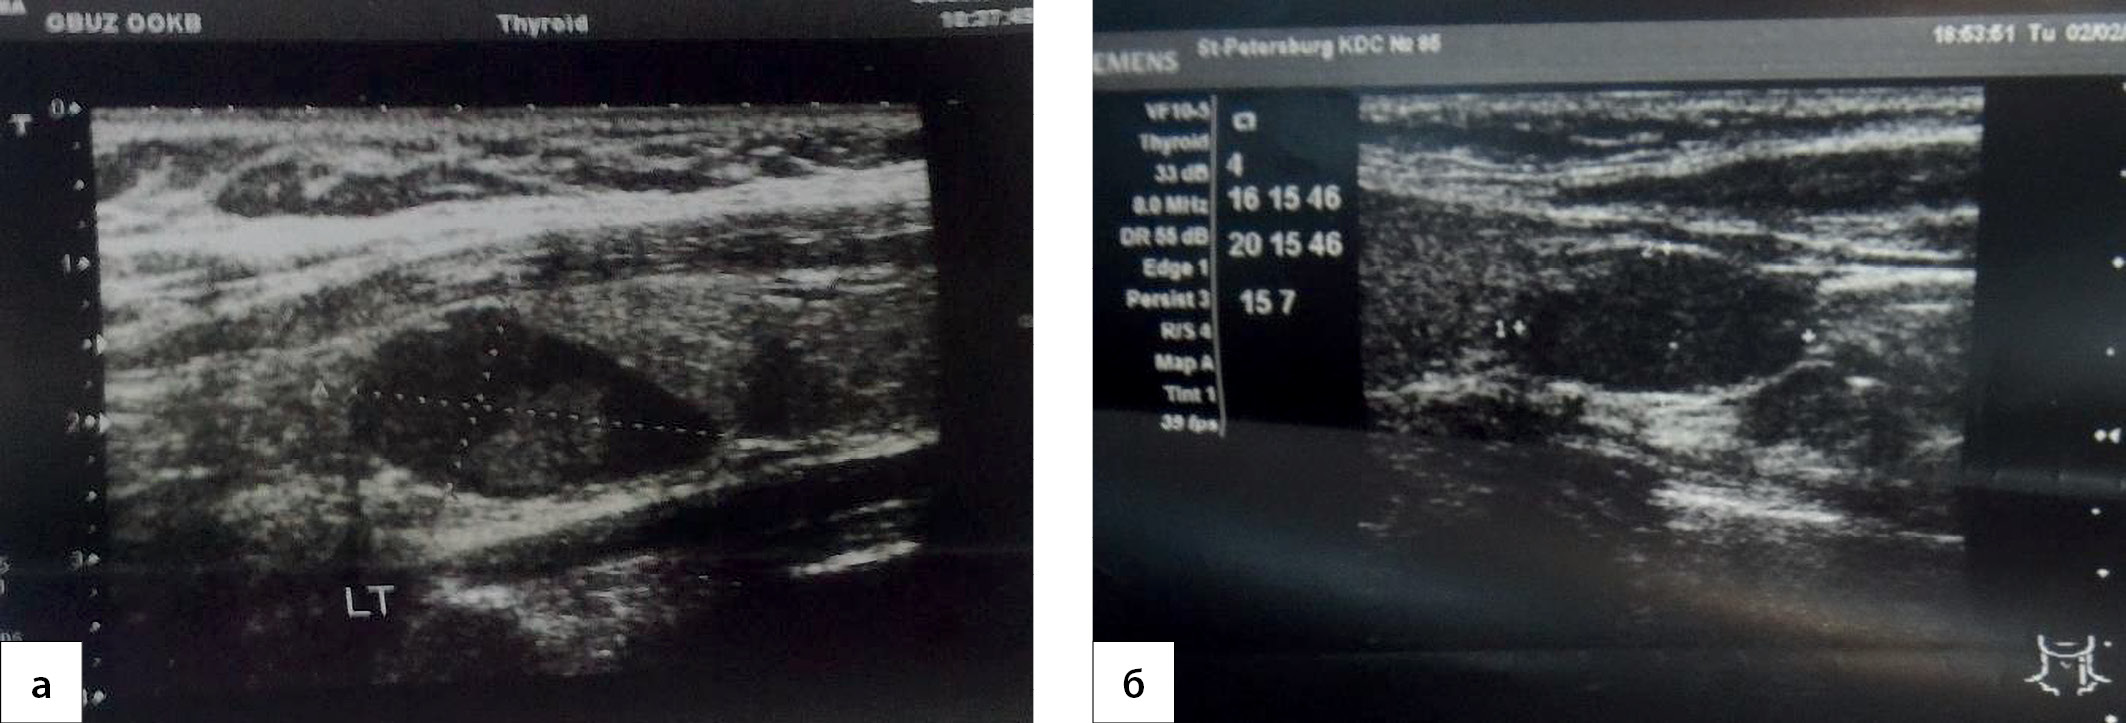

1. Рис. 1. Ультразвуковое исследование: а), б) аденомы околощитовидных желез.